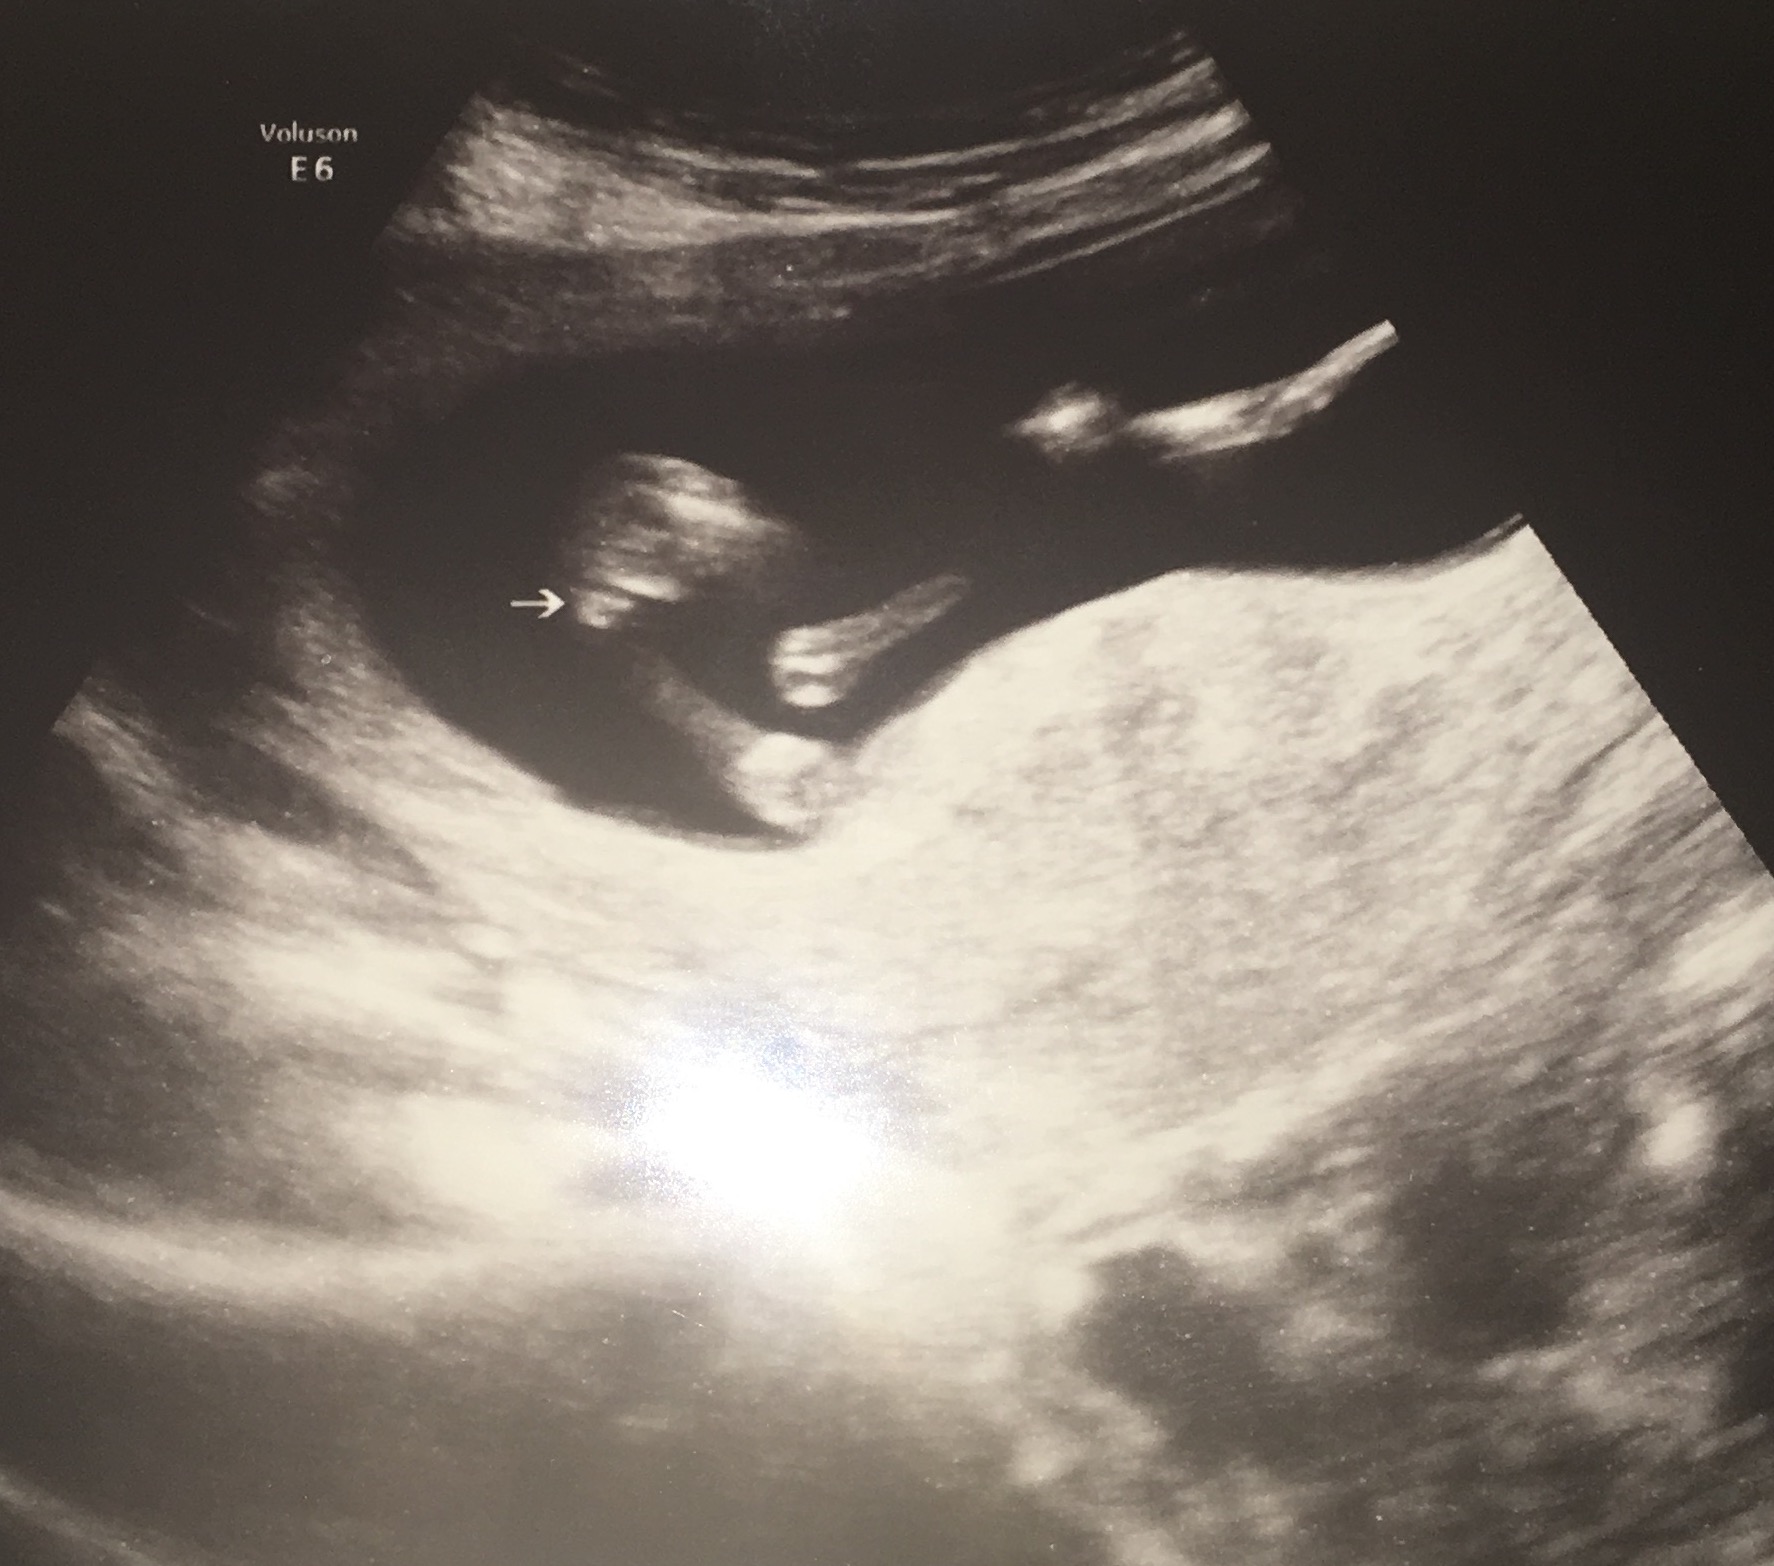

I had an elective gender scan at 15 weeks and the tech said that she was FOR SURE on the gender but

I just am not sure when I look at 2 of the 3 potty shots she gave me. I want it to be what she claims it is but I am just feeling a little unsure. Please give your input, it will be very very appreciated!! Attachment 36811Attachment 36812Attachment 36813